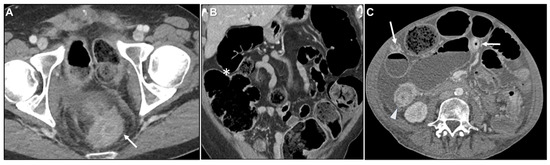

Malignant Target Sign

- Gollub, M.J.; Schwartz, M.B.; Shia, J. Scirrhous metastases to the gastrointestinal tract at CT: The malignant target sign. AJR Am. J. Roentgenol. 2009, 192, 936–940. [Google Scholar] [CrossRef][Green Version]